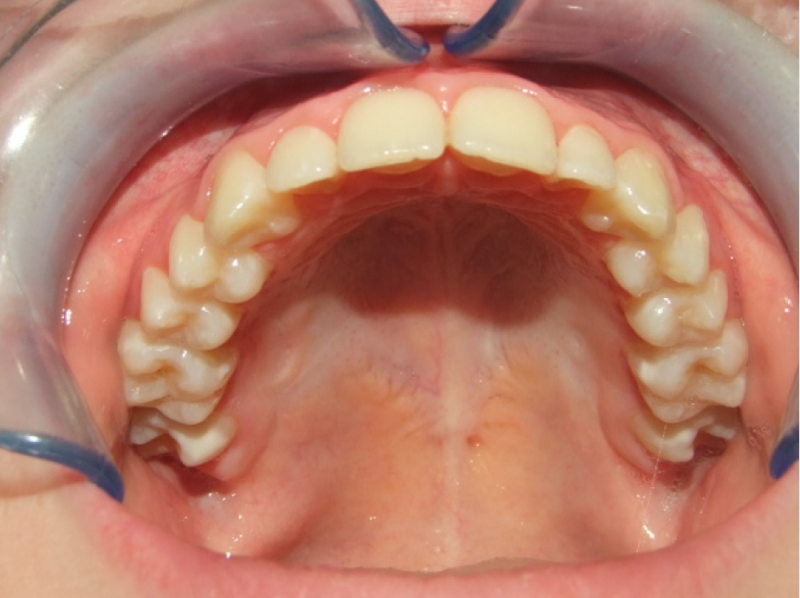

1-6 Bonded Hyrax + volledig vast onderkaak & TransForce

14-26 volledig vast boven- en onderkaak + TPA